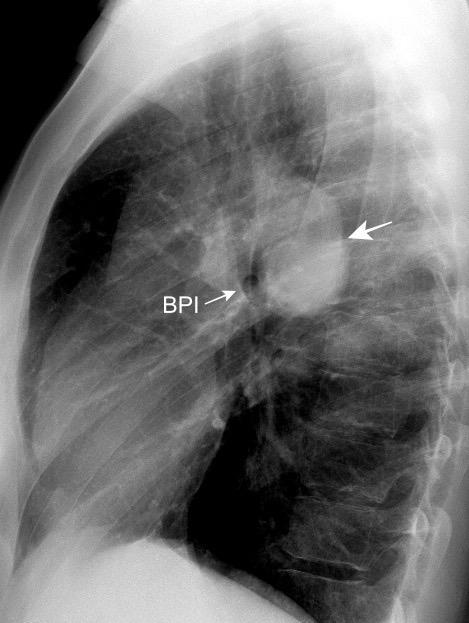

Anatomía

BPI: 75% de normales

La imagen es probable que represente al BPI, a la altura del nacimiento del BLSI.

AV,. The left lateral radiograph of the chest. Part One. Med. Radiogr. Photogr.1979.

La presencia de tumor o ganglios rodeando el BPI hace que este aparezca como mucho más nítido y definido.

Carcinoma microcítico..

Parálisis frénica. Atelectasia parcial de LSI.

Whitten CR. A Diagnostic Approach to Mediastinal Abnormalities. Radiographics 2007 / Marano R et al. Cardiac Silhouette findings And mediastinal lines and stripes. Chest. 2011

En el normal, el bronquio intermediario (BI) aparece en la proyección lateral, como una línea fina vertical que cruza el bronquio del LSI en su unión con el principal. (BPI) Engrosamiento del bronquio intermediario (BI)

97% de normales

Causas

Fallo cardiaco

Ca de pulmón

Metástasis

Linfoma

Sarcoidosis

Castleman

Schnur MJ et al.. Thickening of the Posterior Wall of the Bronchus Intermedius. Radiology. 1981